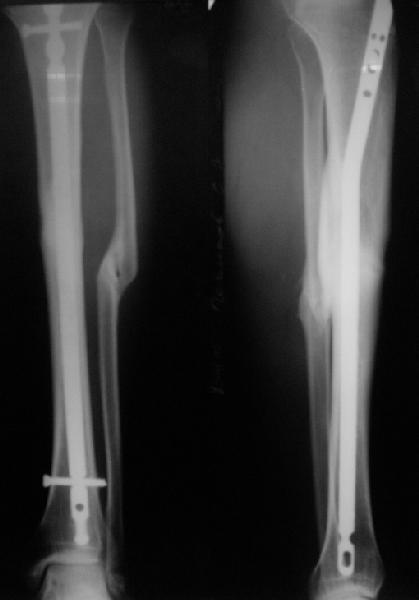

Вот пример, тоже открытый перелом, первичный дефект, пробыл в аппарате 5 мес. Титановый гвоздь, сразу динамический, без покрытия. Больше не делали ничего.